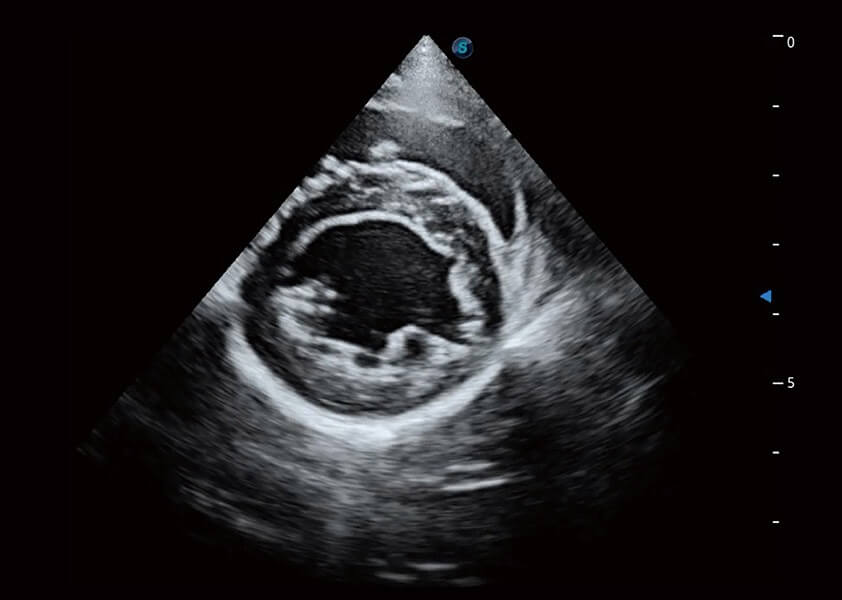

ProPet 60 作为一款高端台式动物超声设备,为动物医生的日常诊断提供了一系列贴合动物临床需求、解决临床实际问题的高级成像功能。凭借全系列高清探头,满足医生对腹部、心脏、生殖、浅表、肌骨等成像的所有需求,切实帮助您提升检查效率,提高诊断信心。

动物是人类最亲密的朋友和最值得信赖的伙伴。新葡的京集团8814检测站也一直致力于探索动物专用的超声影像解决方案。 全新推出的ProPet系列,是新葡的京集团8814检测站在动物超声影像智能化、专业化、精准化的一次跨越式革新。动物不能用言语来表述自己的不适,通过超声影像,ProPet系列搭建了动物医生与不同物种沟通的“桥梁”,为动物医生注入了“治愈之力”。